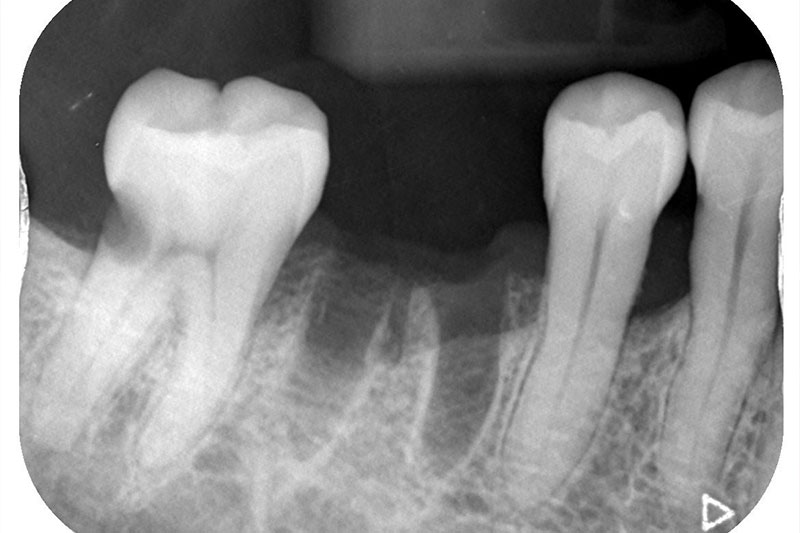

レントゲン写真およびCT画像なのですが、右上6が残歯状態であり歯根破折を起こしている状態でした。しかし歯槽骨から上顎洞底までの距離は十分に認められます。この歯槽骨から上顎洞までの距離がないとソケットリフトなどのオプションの処置が必要になってくるのですが、今回の症例では大掛かりな処置の必要はなく症例の難易度としては比較的イージーな方でした。上顎洞などに関して知りたい方はこちらのページを参照にしていただければと思います。